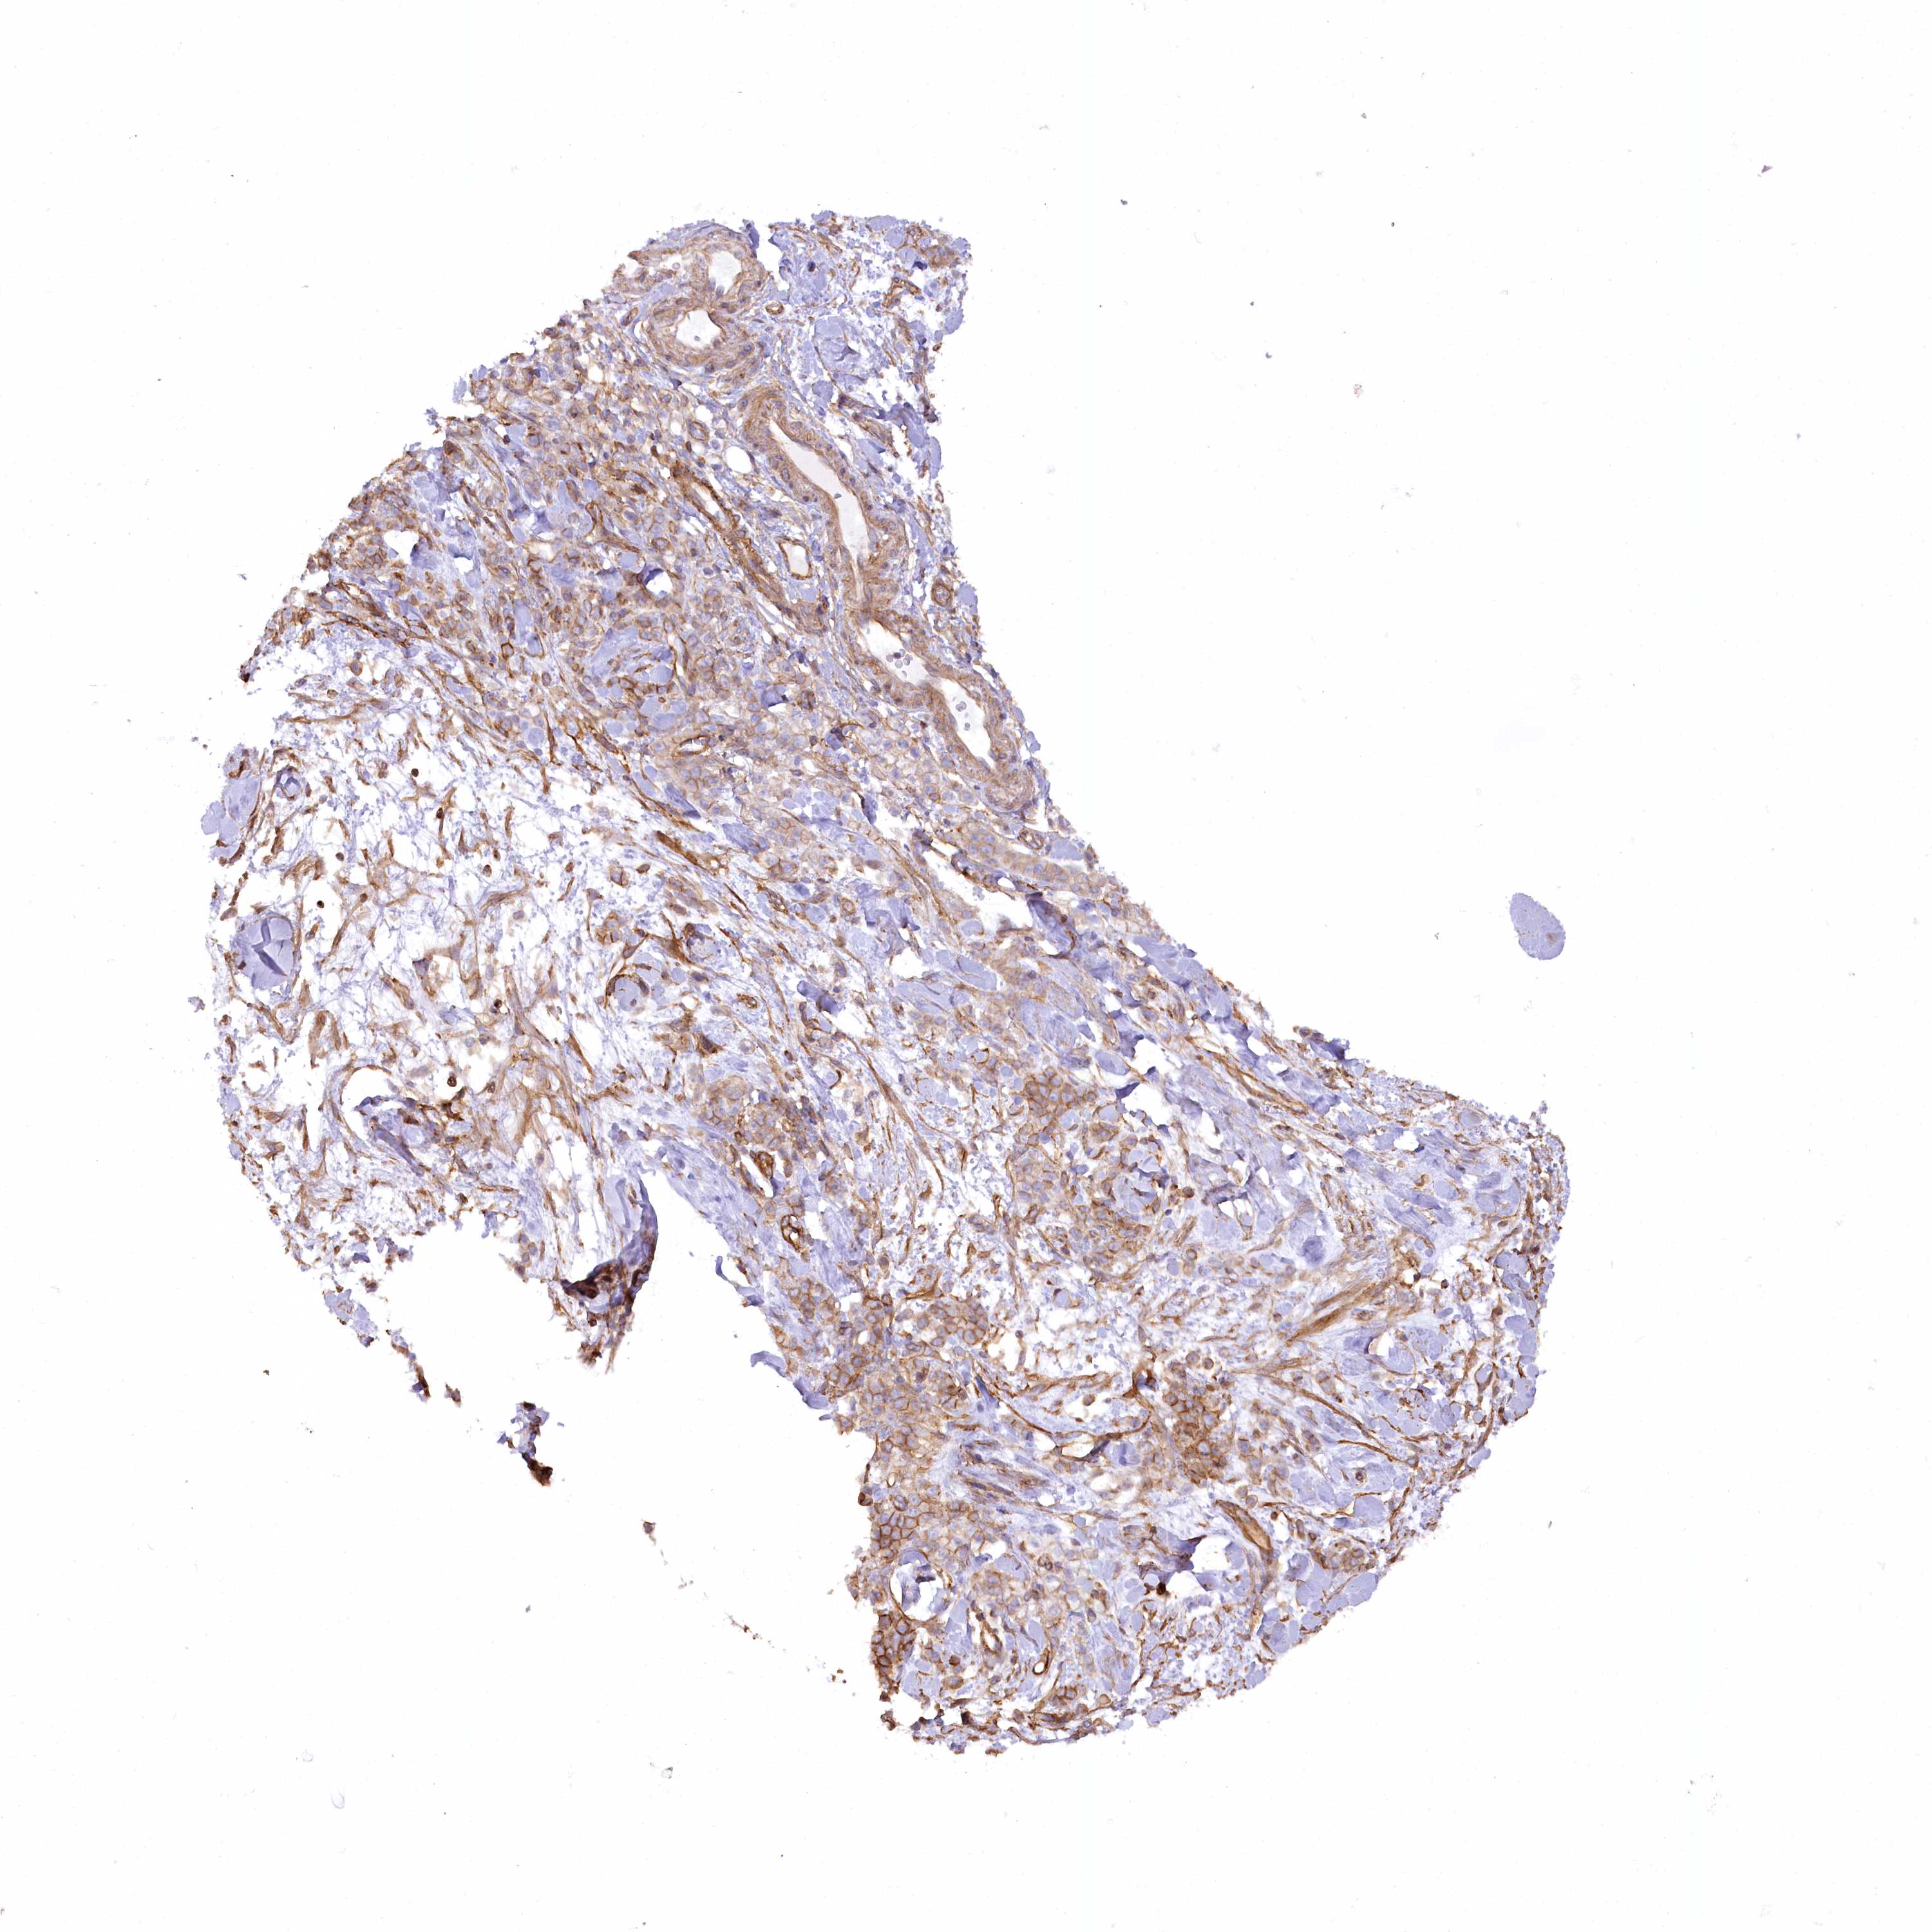

STOMACH CANCER - Protein expressioni

A mouse-over function shows sample information and annotation data. Click on an image to view it in a full screen mode. Samples can be filtered based on level of antibody staining by selecting one or several of the following categories: high, medium, low and not detected. The assay and annotation is described here.

Note that samples used for immunohistochemistry by the Human Protein Atlas do not correspond to samples in the TCGA dataset.

Antibody stainingi

Antibody staining in the annotated cell types in the current human tissue is reported as not detected, low, medium, or high, based on conventional immunohistochemistry profiling in selected tissues. This score is based on the combination of the staining intensity and fraction of stained cells.

Each image is clickable and will lead to virtual microscopy that enables deeper exploration of all samples and also displays staining intensity scores, fraction scores and subcellular localization as well as patient and tissue information for each sample.

Antibody HPA030665

Antibody HPA068563

Antibody CAB037231

Staining

High

Medium

Low

Not detected

Intensity

Strong

Moderate

Weak

Negative

Quantity

>75%

75%-25%

<25%

None

Location

Nuclear

Cytoplasmic/membranous

Cytoplasmic/membranous,nuclear

Adenocarcinoma, NOS